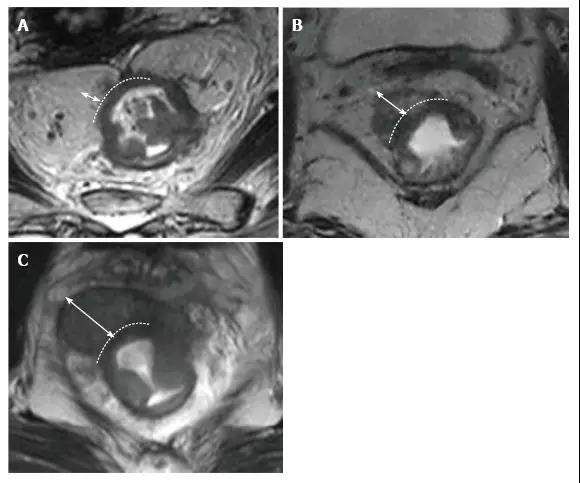

图 5. 女性(A 和 B)和男性(C 和 D)腹膜受侵 T4a 直肠肿瘤患者。在矢状位 T2 加权图像上,腹膜是肿瘤前面的低信号线性结构(A,C 中的箭头)。在轴位 T2 加权图像上,腹膜具有 V 形并且附着在直肠癌的前面(B 和 D 中的箭头)。T:肿瘤;U:子宫;P:前列腺。